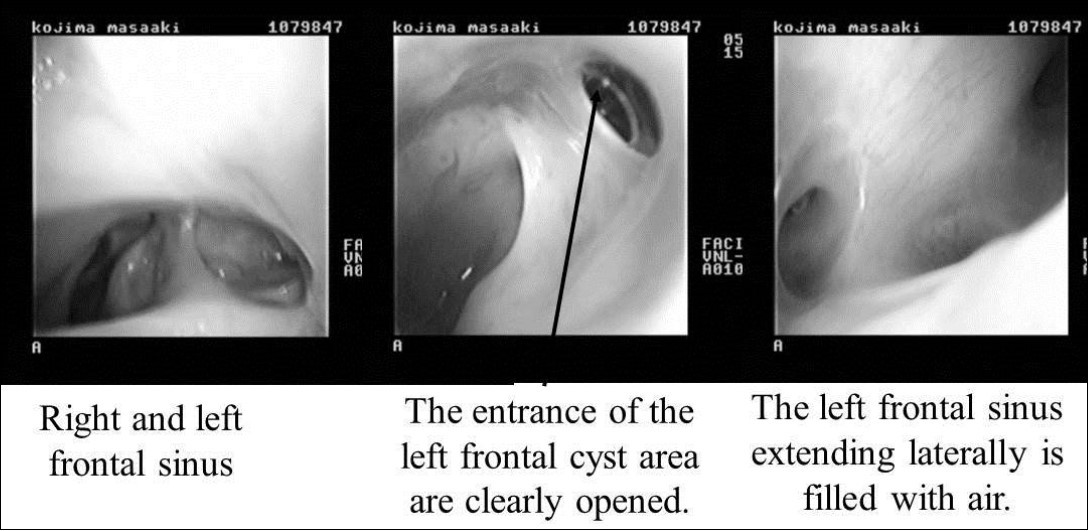

On April 16, 2008, reoperation was performed to place a ceramic implant, but some pus was found in the left lateral sinus. The lesion was debrided, the dead space was filled with muscle, and surgery was completed without ceramic implantation. On October 17, 2008, another surgery confirmed that the frontal sinus was clean, and a ceramic implant was placed. The postoperative course has been good, and as of May 2009, the frontal sinus extending laterally is filled with air (Figure 5, Figure 6).

Figure 6.Endoscopic findings after surgery. Right and left frontal sinuses. The entrance of the left frontal cyst area is clearly opened (black arrow). The left frontal sinus extending laterally is filled with air.